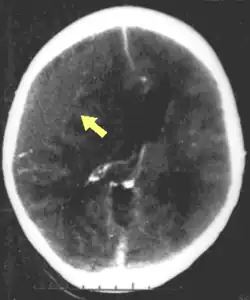

One type of focal injury, cerebral laceration, occurs when the tissue is cut or torn.[37] Such tearing is common in orbitofrontal cortex in particular, because of bony protrusions on the interior skull ridge above the eyes.[31] In a similar injury, cerebral contusion (bruising of brain tissue), blood is mixed among tissue.[23] In contrast, intracranial hemorrhage involves bleeding that is not mixed with tissue.[37]

Hematomas, also focal lesions, are collections of blood in or around the brain that can result from hemorrhage.[11] Intracerebral hemorrhage, with bleeding in the brain tissue itself, is an intra-axial lesion. Extra-axial lesions include epidural hematoma, subdural hematoma, subarachnoid hemorrhage, and intraventricular hemorrhage.[38] Epidural hematoma involves bleeding into the area between the skull and the dura mater, the outermost of the three membranes surrounding the brain.[11] In subdural hematoma, bleeding occurs between the dura and the arachnoid mater.[23] Subarachnoid hemorrhage involves bleeding into the space between the arachnoid membrane and the pia mater.[23] Intraventricular hemorrhage occurs when there is bleeding in the ventricles.[38]